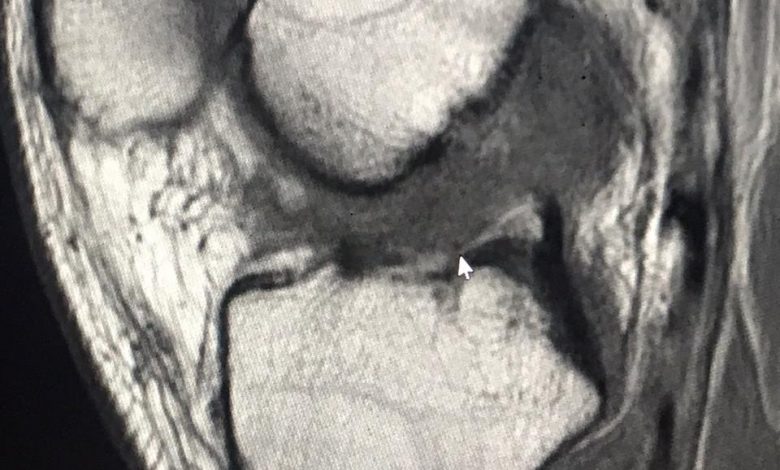

‫نجح فريق طبي بمستشفى القريات العام  في إجراء  14 عملية إعادة بناء رباط صليبي أمامي للركبة بإستخدام الأوتار الخلفية للركبة وكذلك إجراء 4 حالات خياطة‬

‫و إصلاح الغضروف الهلالي للركبة عن طريق المنظار بثلاث فتحات صغيرة  مما أدى إلى عودته إلى الوضع الطبيعي ‬.